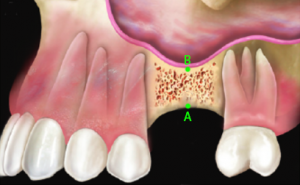

2. Viene perciò preparato un foro d’accesso nel tessuto osseo. |

3. Fino ad arrivare all’inizio del seno mascellare. |